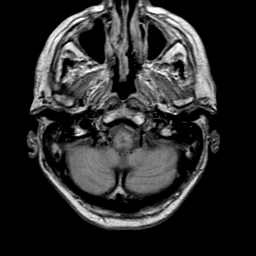

Meningioma, MR Study #1 -- Slice #1

[Home][Help][Clinical] Slice 1